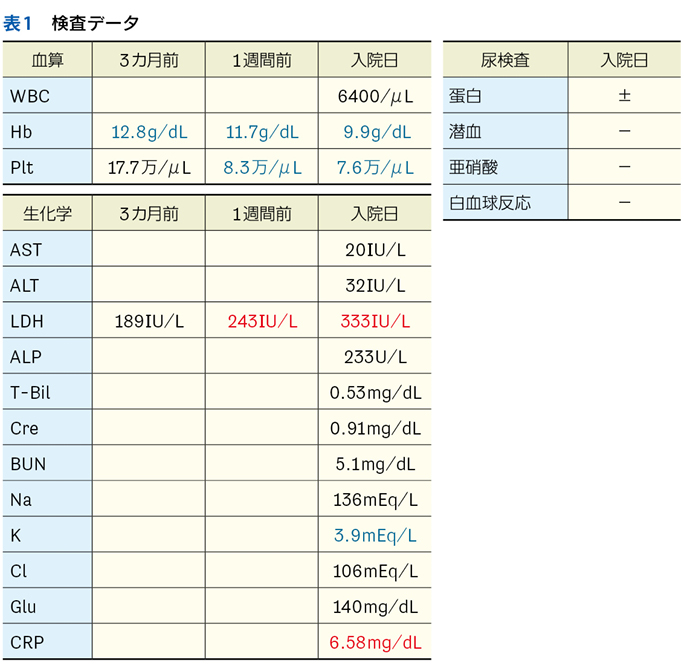

▶ こちらは初期評価不十分のまま多数の介入がなされたケースである。患者が呈している「プロブレム」をまとめて,「皮疹,肝機能異常,腎障害,汎血球減少を伴う遷延性発熱」とフレーミングし,たとえば血管内リンパ腫や血球貪食を伴う成人スティル病などを考えることも可能だが,現在の症状や検査異常(の一部)は抗菌薬をはじめとした介入の副作用として生じているのかもしれない。すべてのプロブレムが一元論で説明されない可能性も考慮したフレーミングも用意するのが謙虚な態度だろう。